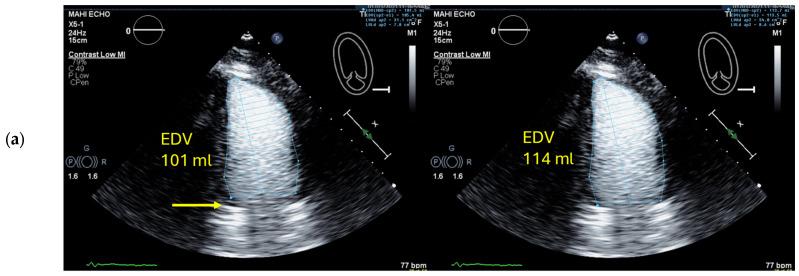

How to Perform Cardiac Contrast-Enhanced Ultrasound (cCEUS): Part I.

Ultrasound enhancing agents (UEAs, formerly called contrast agents) for assessments of the left heart have improved the applicability of echocardiography and the accuracy of echocardiographic measurements. UEAs have been recommended for several diagnostic echocardiographic procedures by national and supernational agencies. The increased use of UEAs during the last years provided more evidence and experience in clinical practice data which is helpful for optimizing the UEA procedures and which will be useful for both newcomers to UEA in echocardiography and sonographers/physicians with experience in echocardiography with UEAs. In two parts, this review focuses on the "how to do" for the approved UEA applications. This is part 1, covering the available UEAs and providing specific guidance on the assessment of global and regional LV function. Part 2 covers the imaging of myocardial disease and masses as well as myocardial perfusion. Recommendations include the application of UEAs in two-dimensional echocardiography as there is limited data on three-dimensional echocardiography. A step-by-step approach is proposed for each of the procedures as well as guidance on how to interpret recordings and how to report them.